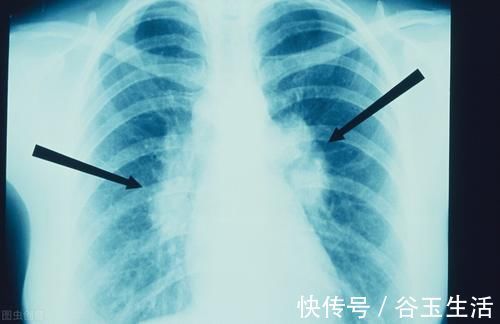

对于早期肺癌,一般通过手术切除都能取得不错的治疗效果,很多患者术后往往都没有太多的影响,可以达到临床治愈的效果,所以早期发现早期治疗是非常关键的。

而对于肺小结节的随访时间,一般是以三个月、半年、一年等为单位选择合适的随访时间,比如你的肺小结节小于5mm,那么一年随访复查一次就可以了,因为你随访得太频繁,可能造成不必要的过度检查,而如果随访间隔太长,则有可能耽误病情,所以对于随访时间,大家一定要咨询专科医生,根据自己的情况,制定最科学合理的随访时间。